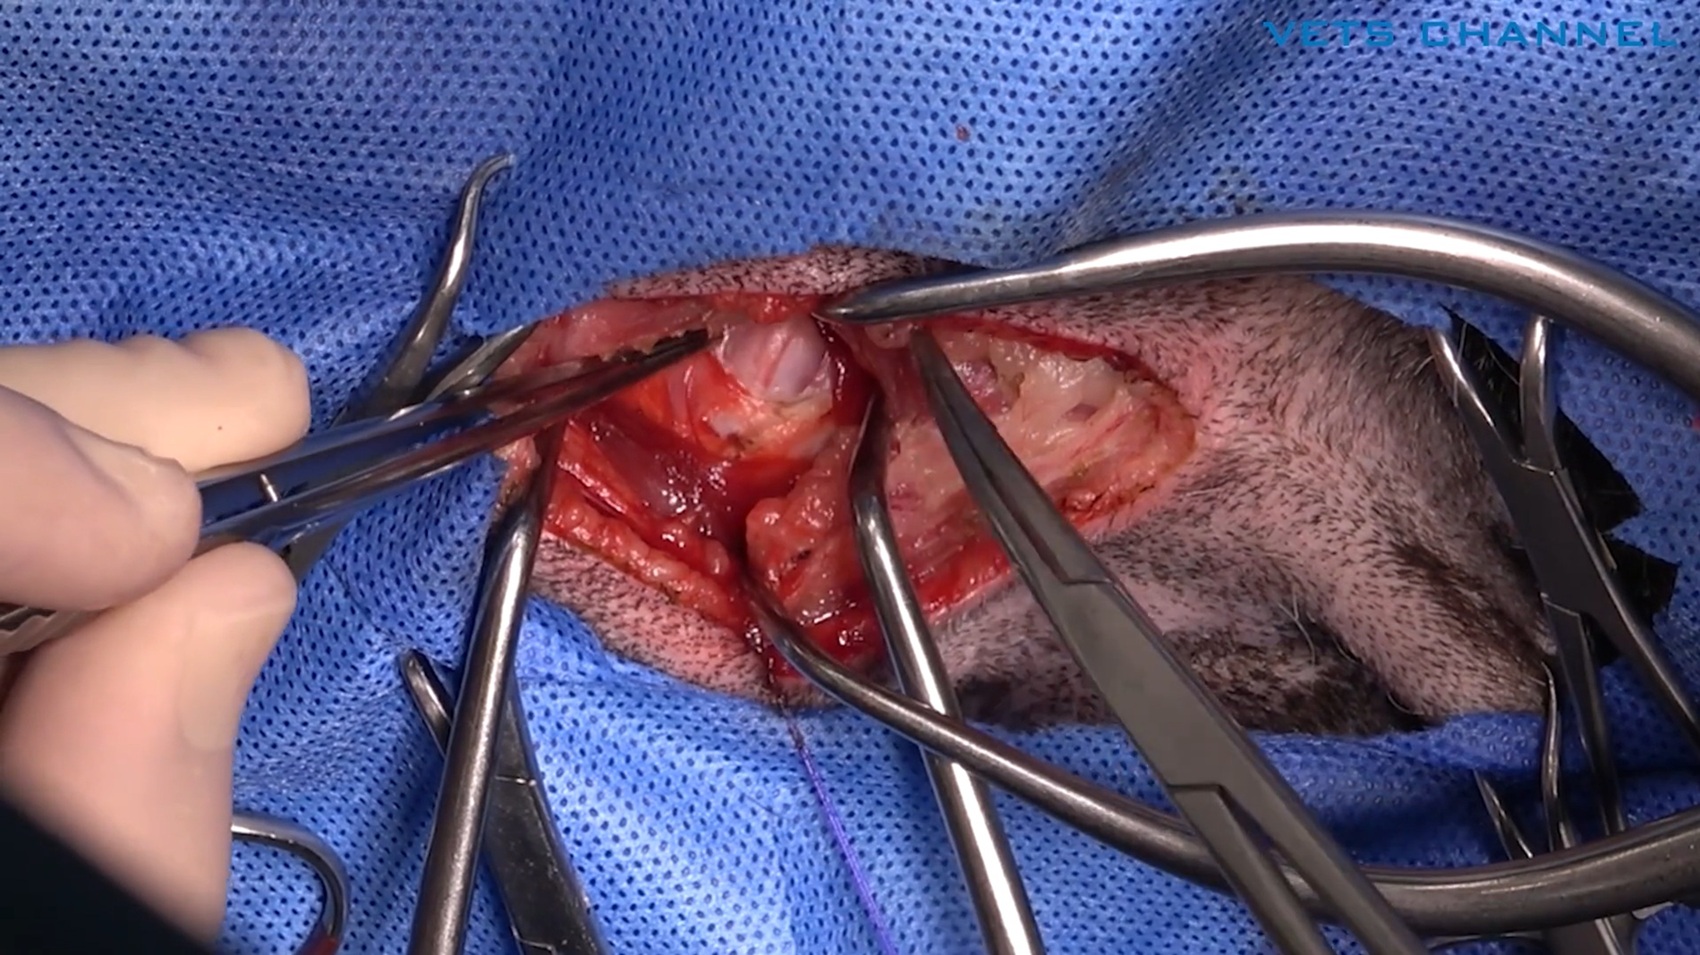

局所再発した扁平上皮癌に対する両側下顎切除術

- OPE

- 軟部外科

- 歯科・口腔外科

- 腫瘍科

- 猫

藤本 晋輔先生 (大津どうぶつ医療センター)

20分

2025/11/14

局所再発した扁平上皮癌に対する両側下顎切除術

- OPE

- 軟部外科

- 歯科・口腔外科

- 腫瘍科

- 猫

藤本 晋輔先生 (大津どうぶつ医療センター)

20分

2025/11/14

局所再発した扁平上皮癌に対する両側下顎切除術

- OPE

- 軟部外科

- 歯科・口腔外科

- 腫瘍科

- 猫

藤本 晋輔先生 (大津どうぶつ医療センター)

20分

2025/11/14